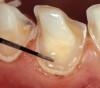

The next steps can include the application of either the primer (3-step systems) or the self-priming resin (2-step systems). Practically, the separate primer application should be favored (Figures 2H through 2J), not only because of the superior subsequent bond but also because it allows a more accurate placement of the adhesive resin. In fact, the application of a priming agent or self-priming resin often requires a slight brushing motion, which frequently results in the spread of resin above the exposed dentin limits. There are no consequences when using a separate primer as the latter does not create any detectable thickness or layer. After the suction of the excess solvent (Figure 2J), the adhesive resin can be placed accurately (eg, with a periodontal probe, as in the case of veneer preparation margins [Figures 2K through 2N). On the other hand, the use of self-priming resins generates excesses and may pull over the margin (into the gingival sulcus), requiring additional corrections with a bur, again exposing dentin at the margin.

Figure 2c  A marked gingival chamfer always facilitates  the application of the dentin bonding  agent. Immediate dentin bonding would not  be possible in the presence of a traditional  light chamfer because the adhesive layer  tends to pull over the margin, creating a feather-  edge finish line and insufficient margin  definition.

Figure 2c

Figure 2k  The adhesive is applied  with precision using a drop of resin on  the tip of a periodontal probe. Direct contact  between the dentin and the tip of the probe  should be avoided. The probe is used to  help spread the adhesive to the edges of  the exposed dentin.

Figure 2k

Figure 2l  The adhesive is left  to diffuse along the chamfer. The tip of the  probe should not approach the margin more  than 0.5 mm to avoid pulling of the resin (red  rectangle shows a magnified view of gingival  dentin margins seen in image M).

Figure 2l

Figure 2m  Because  of surface tension phenomenon, the  adhesive spreads onto the primed dentin  surface but is arrested at the sharp edge of  the margin.

Figure 2m

Figure 2n  Because of the original deep  chamfer, the definition of the margin is not  affected by the presence of the adhesive  laye.

Figure 2n